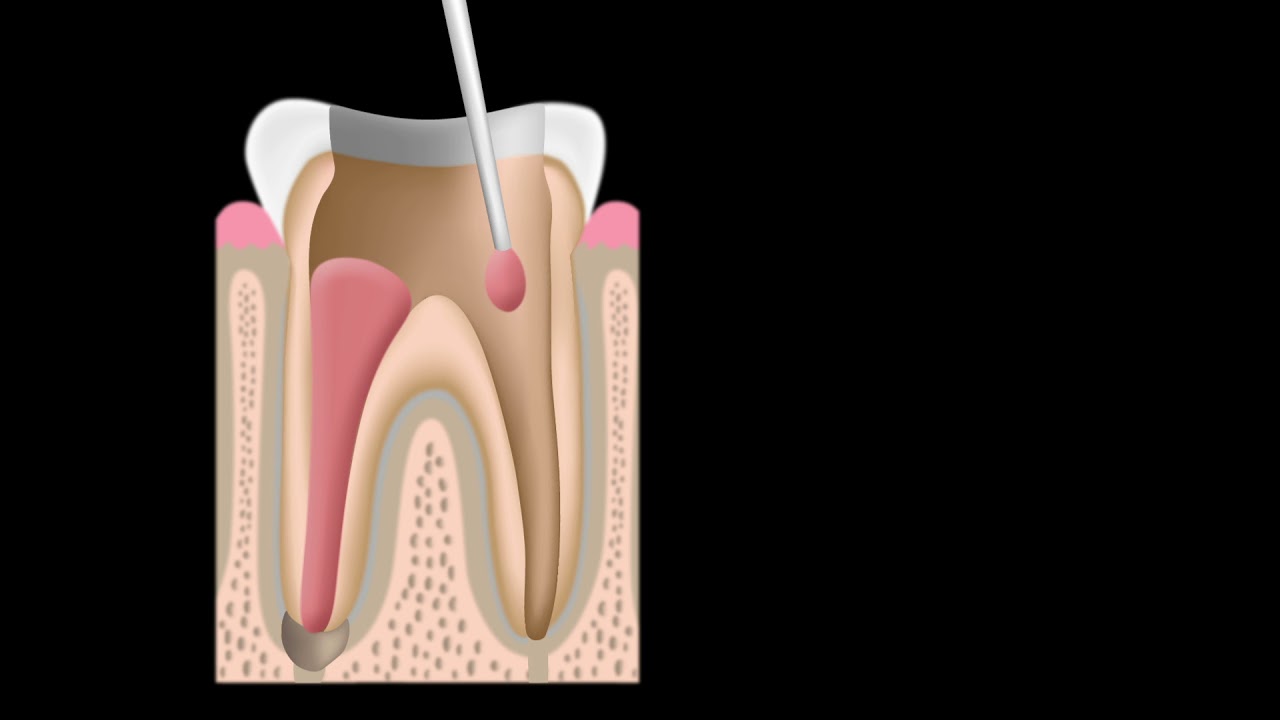

Still worried about the actual procedure? Let 209 NYC Dental clear your mind: A root canal procedure is performed when the pulp of a tooth becomes infected, inflamed, or dies.

Causes of these conditions include deep decay, a fracture in the tooth, or trauma to the tooth. The procedure for a root canal in NYC involves making a small access opening in the tooth after administering dental anesthesia. Using small, thin, sterile instruments called endodontic files, the dentist then cleans and shapes the small, thin canals of the tooth.

After the canal(s) is/are cleaned and shaped, a biocompatible material, called gutta-percha, is placed within the canal(s) with a special adhesive cement to make sure that no other bacteria or debris enter the canal(s).

Because our root canal specialists use cutting-edge technology to perform procedures, they’re able to detect even the smallest canal branches that the naked eye could easily miss. This level of precision helps prevent our patients from reinfections and improves their long-term outcomes.